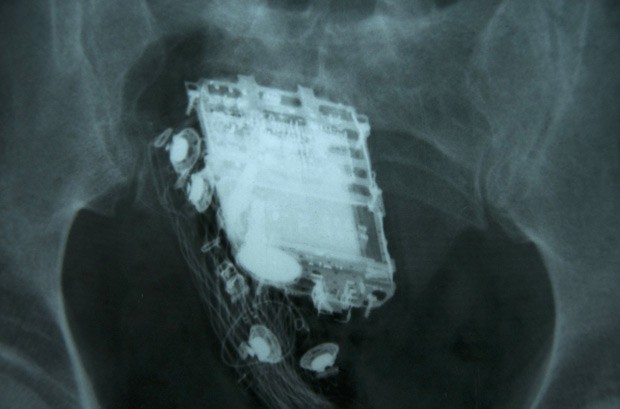

O condenado de 58 anos de idade precisou ser internado no hospital nacional em Colombo, onde os médicos mais tarde retiraram o aparelho de seu reto.

"O homem tinha escondido o telefone dentro dele mesmo", disse o funcionário, que pediu para não ser identificado.